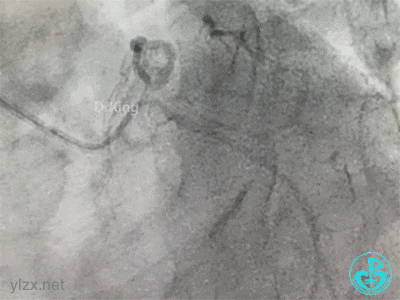

冠脉造影

右冠脉近中段不规则狭窄。短左主干中度狭窄,前降支开口严重狭窄,多功能造影导管推注造影剂时无反流,导管退出左主干开口造影发现左主干狭窄严重。